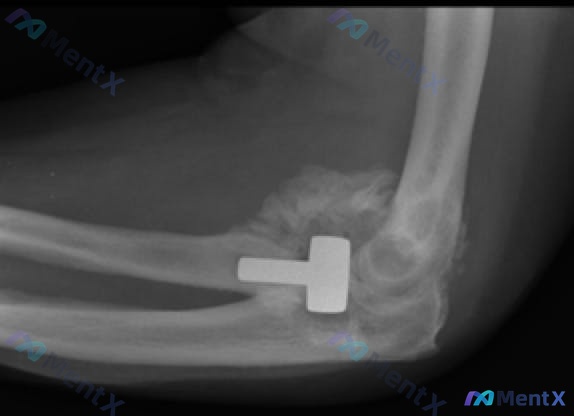

整理了一个比较特殊的骨科病例,前期资料放出来看看大家第一眼思路会不会被带偏。 基本情况:23岁男性,无明显既往史/常规用药史。 病史背景:攀登珠穆朗玛峰时跌倒致粉碎性骨折,因天气恶劣,送往创伤中心的疏散推迟了五天;六周前接受了肘关节置换术(桡骨头置换)。 本次术后随访: - 生命体征:体温 99.1...